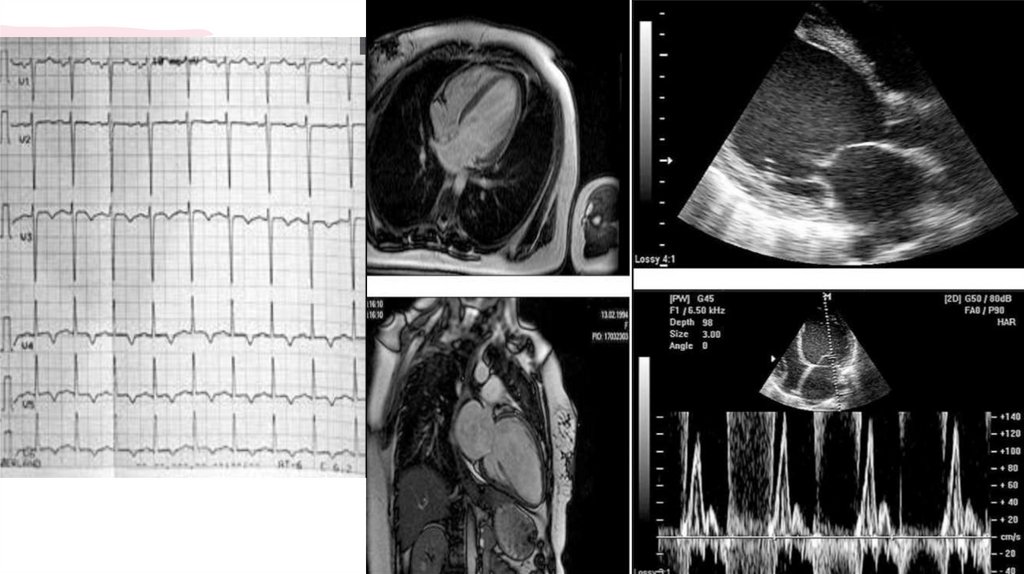

6. Діагностика

ДІАГНОСТИКА